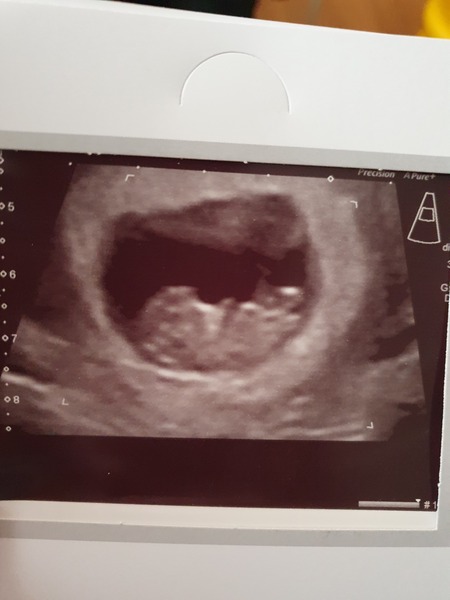

The positives of my scan - heard and saw strong heartbeat and a somersaulting blob!

Anxiety provoking parts - measuring small... initially they dated me 8 days smaller but revised this to about 4 days as the scan went on... it also didn't look anything like anyone else's scans around this stage - it is really unclear and just looks like a very small blob in a very large sac... 🙈

Trying to hold onto the positives of the day - the sonographer said it looked positive and the movement was a positive sign!

@didslysquiddlydoo the fact you heard heartbeat is amazing! Scan pics can be hard to get clear images. Especially if your little one was squirming and somersaulting all over lol. We were fortunate to get quite a clear one for our 10 week checkup but it took her 10 mins to get it as Pip wouldn't stop wiggling haha. Glad it was a good scan and I'm sure they will catch up in size soon xx